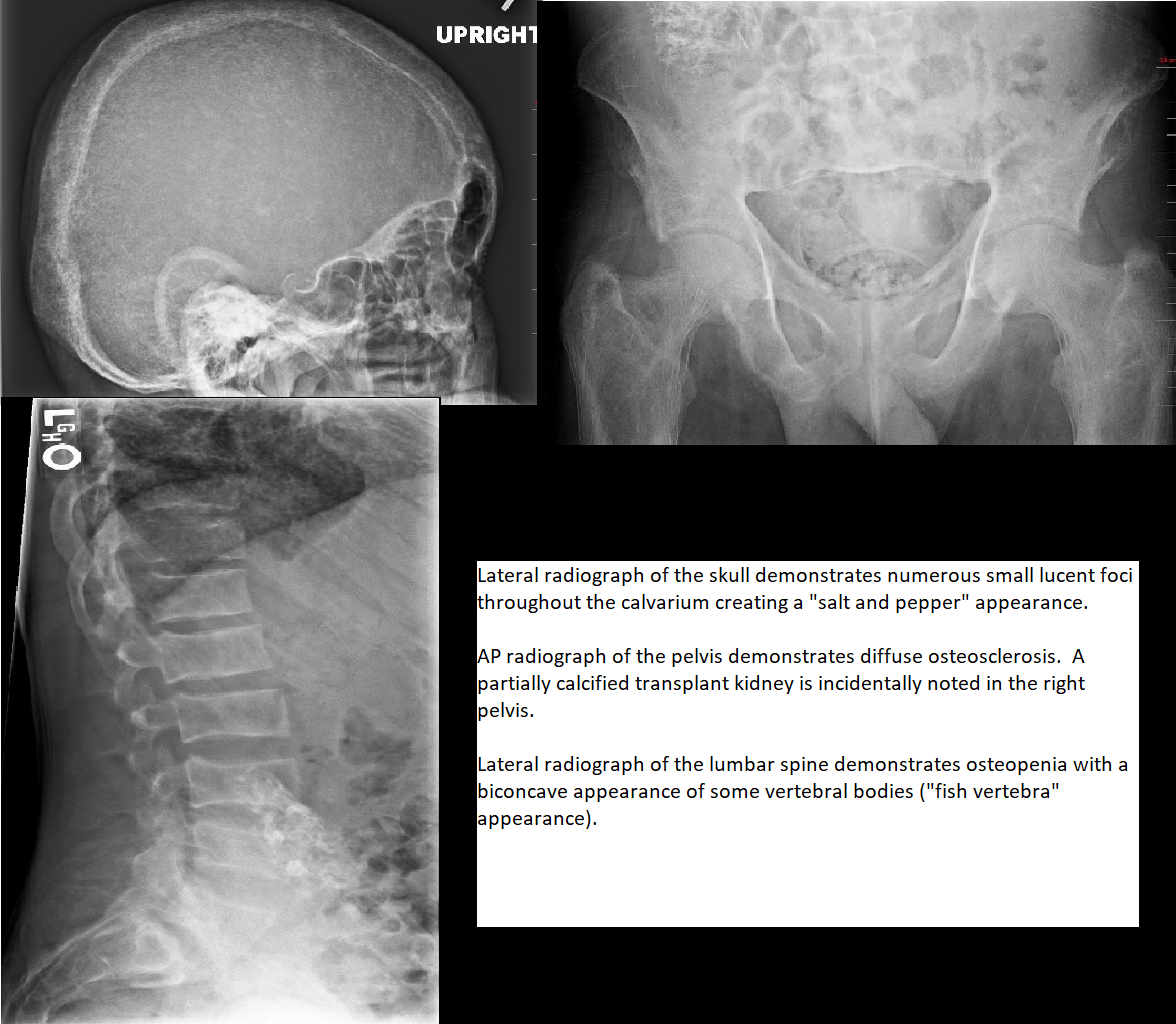

4) Brown tumors. Expansile well-defined geographic lytic lesions with narrow zone of transition. (mandible, hands, pelvis, ribs)

1. Osteopenia

2. Osteosclerosis (diffusely coarsened trabeculae, rugger jersey spine, salt and pepper skull; UNLIKE pagets which is usu not so uniform)